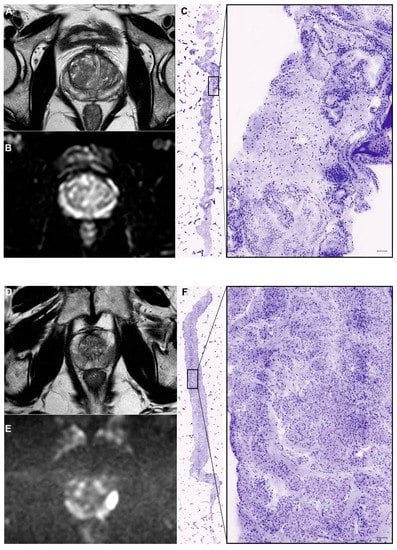

- Rocco, B.; Sighinolfi, M.C.; Sandri, M.; Spandri, V.; Cimadamore, A.; Volavsek, M.; Mazzucchelli, R.; Lopez-Beltran, A.; Eissa, A.; Bertoni, L.; et al. Digital Biopsy with Fluorescence Confocal Microscope for Effective Real-time Diagnosis of Prostate Cancer: A Prospective, Comparative Study. Eur. Urol. Oncol. 2020, 4, 784–791. [Google Scholar] [CrossRef]

- Selvaggio, O.; Falagario, U.G.; Bruno, S.M.; Recchia, M.; Sighinolfi, M.C.; Sanguedolce, F.; Milillo, P.; Macarini, L.; Rastinehad, A.R.; Sanchez-Salas, R.; et al. Intraoperative Digital Analysis of Ablation Margins (DAAM) by Fluorescent Confocal Microscopy to Improve Partial Prostate Gland Cryoablation Outcomes. Cancers 2021, 13, 4382. [Google Scholar] [CrossRef] [PubMed]